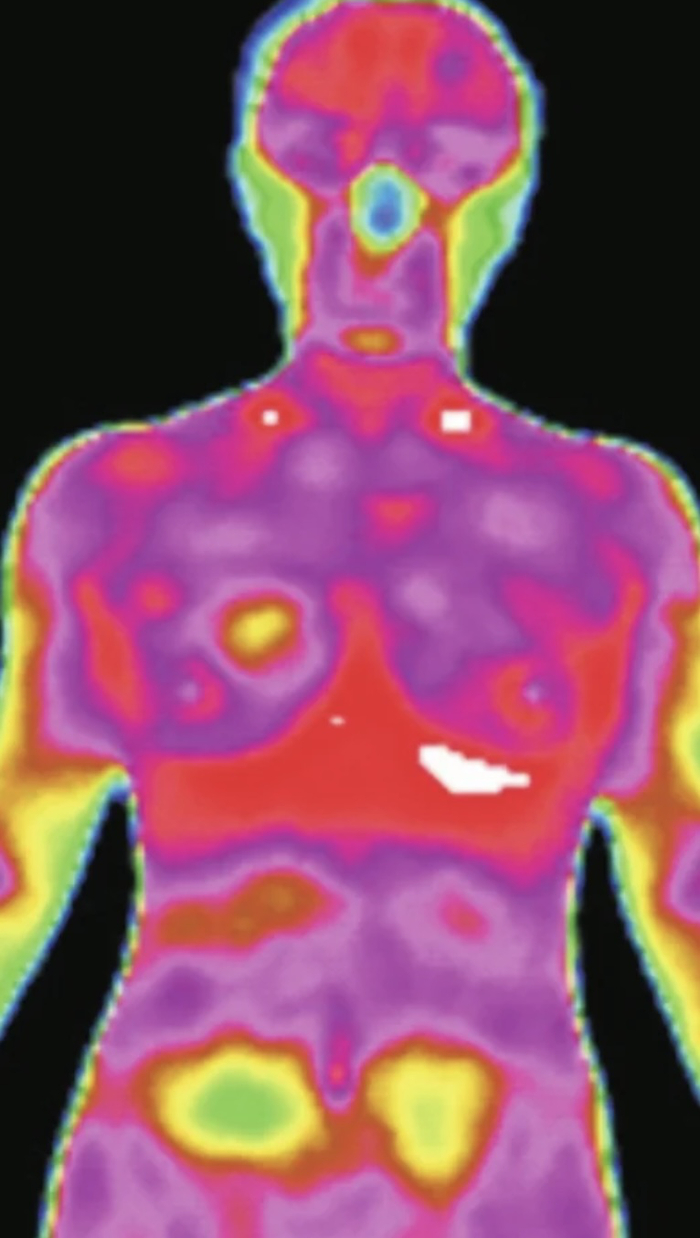

孙丹等研究了红外热成像技术在肝硬化早期的红外热图,发现不同证型的患者体表肝区投影区存在温带变化,得出温度、定位及温带形状可以作为红外热成像技术诊断肝硬化早期的关键指标之一。